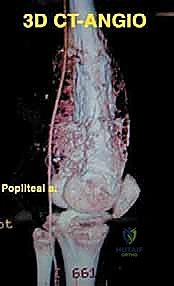

الخطوة الأولى: الوصول الجراحي الآمن وعزل الأوعية الدموية

يبدأ الجراح بعمل شق طولي دقيق. الأولوية القصوى هنا هي تحديد وعزل الشريان والوريد المأبضي (Popliteal vessels) والعصب الوركي لضمان عدم تضررها أثناء استئصال الورم.

معرض الحالات الإشعاعية: توثيق النجاح الطبي مع د. محمد هطيف

الصور الإشعاعية قبل وبعد الجراحة هي الدليل القاطع على دقة ونجاح الإجراء الطبي. نستعرض هنا مجموعة من الصور التي توضح حجم الإنجاز الطبي في استبدال العظم المصاب بمفصل معدني متطور.